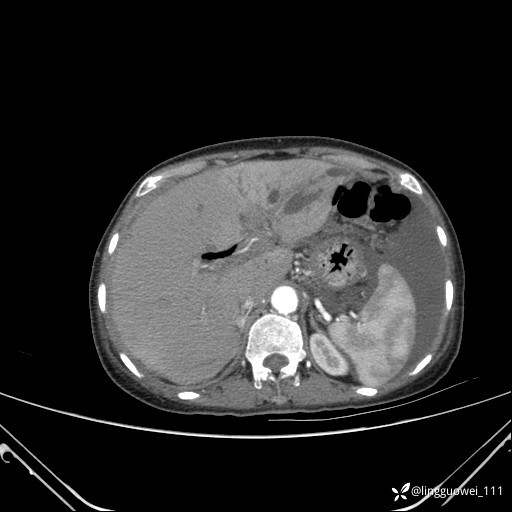

主诉:门诊行胃肠镜检查后,诉腹胀,入院检查,肝有病变吗?腹膜及腹腔的表现有特征性吗?

平扫: